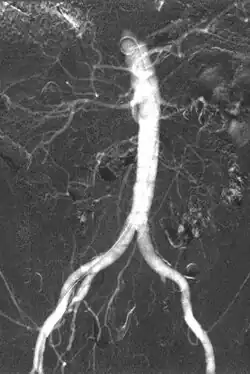

Iodinated contrast contains iodine. It is the main type of radiocontrast used for intravenous administration. Iodine has a particular advantage as a contrast agent for radiography because its innermost electron ("k-shell") binding energy is 33.2 keV, similar to the average energy of x-rays used in diagnostic radiography. When the incident x-ray energy is closer to the k-edge of the atom it encounters, photoelectric absorption is more likely to occur. Its uses include:

- Angiography (arterial investigations)